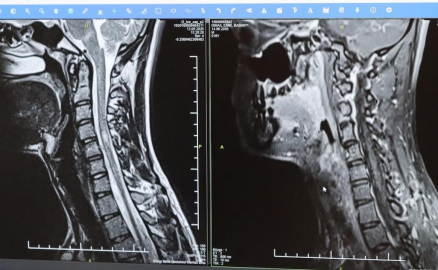

Bursa Şehir Hastanesinde görevli Nöroloji Uzmanı Prof. Dr. Özden Kamışlı, 30 Mayıs Dünya MS Günü kapsamında açıklamalarda bulundu. MS’in, bağışıklık sisteminin sinir sistemine saldırmasıyla gelişen kronik bir hastalık olduğunun bilgisini veren Prof. Dr. Kamışlı, "Dünyada yaklaşık 2.8 milyon MS hastası olduğu bilinmektedir. MS genellikle 20-40 yaş arası gençleri etkilemektedir. Bununla birlikte çocukluk döneminde ya da ileri yaşta da ortaya çıkabilmektedir. Kadınlarda görünme sıklığı erkeklere göre bir buçuk kat daha fazladır" dedi.

MS hastalarının çeşitli şikâyetlerle hekimlere başvurduğunu vurgulayan Kamışlı, "Bunlar arasında görme bozukluğu, kol ve bacakta kuvvetsizlik, uyuşmalar, dengesizlik, yürüme bozukluğu, idrar problemleri veya aşırı yorgunluk ve halsizlik hali bulunmaktadır. MS ataklarla seyredebilir ve genellikle en sık görülen formu budur. Birdenbire bir şikâyet ortaya çıkar ve zamanla azalır veya kaybolur. Bir de progresif dediğimiz ilerleyici formu vardır. Bu ilerleyici formda hastalık yavaş yavaş ilerlemektedir. MS her hastada farklı seyreder. Bu nedenle tek tip bir MS hastalığından bahsetmek mümkün değil" şeklinde konuştu.

Tedavide gelişme kaydedildi

Hastalığın tanısını ne kadar erken konulursa ve tedaviye ne erken başlanırsa; hastaların günlük hayatta aktif ve üretken bir şekilde devam etmelerinin o kadar kolaylaştığına dikkat çeken Kamışlı, "Günümüzde MS’le ilgili çok fazla gelişme oldu ve tedavi seçenekleri arttı. MS merkezlerinde bu tedavi seçeneklerine ulaşmaları mümkün. Hastalarımız için doğru tanı, düzenli takip ve uygun tedavi oldukça önem teşkil etmektedir" diye konuştu.